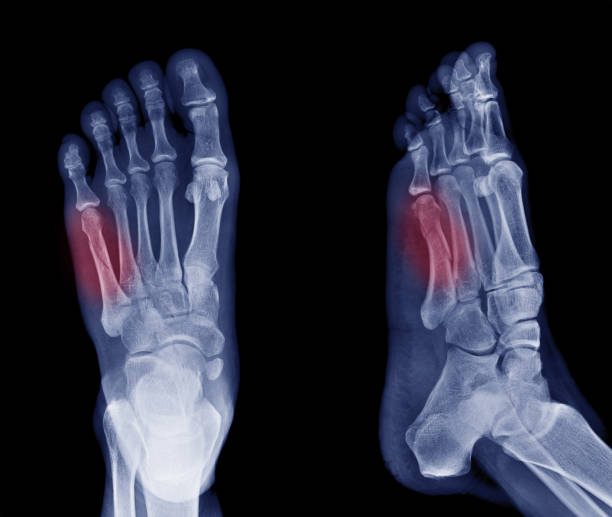

Ultrasonic Therapy for Post-Toe Fracture Rehabilitation Dealing with pain and stiffness after a toe fracture? Are you searching for advanced techniques to speed up recovery? Ultrasonic therapy can be a game-changer in your post-fracture healing journey. Dr. Deepika Bansal, a reliable physiotherapist serving Balewadi, Aundh, Wakad, Pimple Saudagar, and adjoining areas in Pune, offers cutting-edge treatments like ultrasonic therapy. This non-invasive technique uses sound waves to penetrate deep into tissues, promoting: 1. Enhanced Healing – Stimulates blood flow and tissue regeneration. 2. Pain Relief – Reduces inflammation and provides relief from lingering pain. 3. Mobility Restoration – Helps in softening scar tissue and improving joint flexibility. When paired with tailored physiotherapy exercises, ultrasonic therapy can effectively restore function and minimize complications post-toe fracture. Dr. Bansal designs personalized rehabilitation plans to ensure a quicker and smoother recovery process. If you’re searching for a “physiotherapist near me, ” consider Dr. Deepika Bansal for trusted, expert care. Regain your mobility and confidence with the best physiotherapy services today!